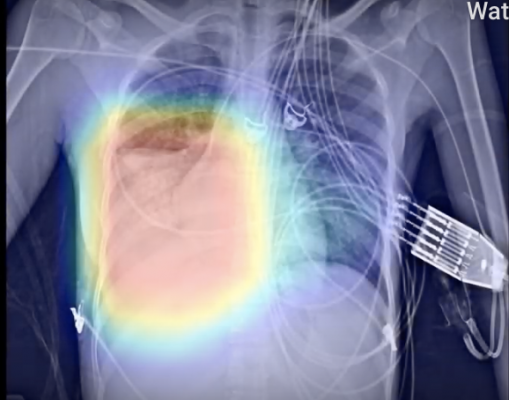

March 23, 2020 — behold.ai announced that its artificial intelligence-based red dot algorithm quickly identifies chest X-rays from COVID-19 patients as ‘abnormal’. This instant triage could potentially speed up diagnosis of COVID-19 individuals and ensure resources are allocated properly.

“The majority of deaths from COVID-19 are owing to pneumonia in the lungs of vulnerable patients. Pneumonia is a potentially life-threatening condition caused by a number of pathogens including, directly or indirectly, COVID-19 infection. Our algorithm can detect abnormal chest X-rays including pneumonia almost instantly. Out of 28 X-rays reviewed from patients with COVID-19, we correctly identified 85% of them as ‘abnormal’ using red dot,” said Tom Naunton Morgan, M.D., MB, FRCS, FRCR, Chief Medical Officer, behold.ai. “As we evaluate further positive cases from across the world, including here in the UK, our results will be further validated. This will increase the utility of our ‘instant triage’ and potentially help reduce the burden on healthcare systems as more and more cases of pneumonia present and require rapid diagnosis.”